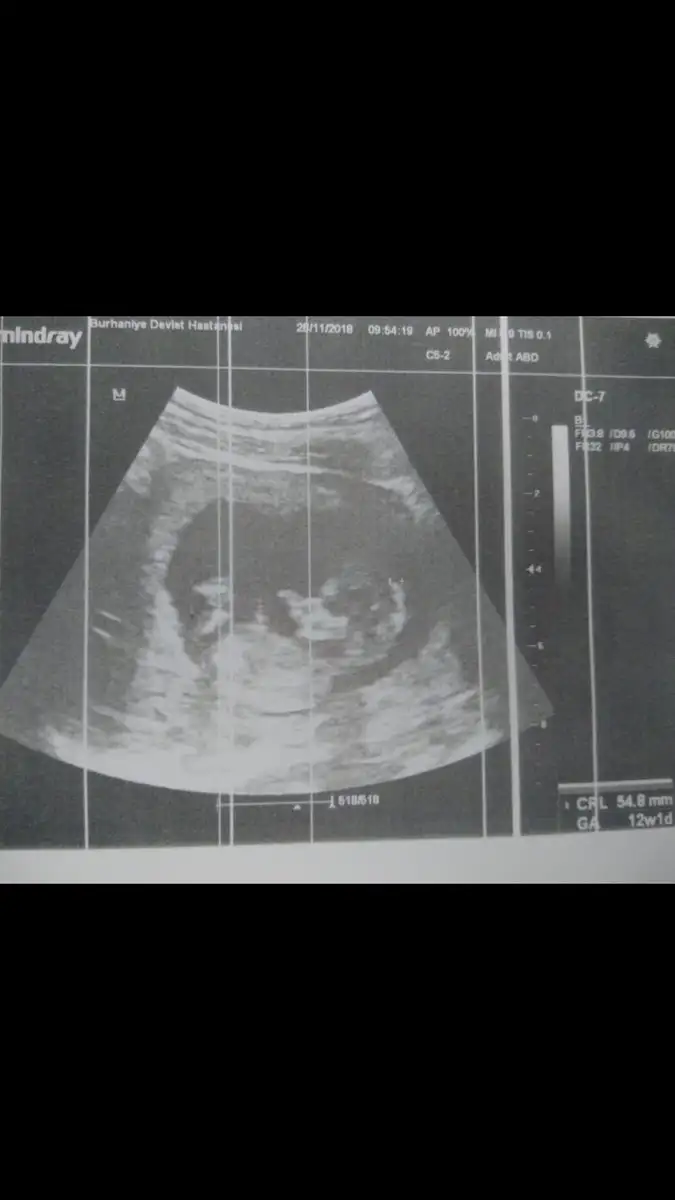

Maşallah bebişine inş lekelenme olmaz birdaha canım . Bidaha ki randevuda öğrenirsin cinsiyeti kesin olması daha iyi yüzde olarak bile söyleseler kesin değil ama heves yapıyoruz hemenBiz geldik kızlar bebiş gayet sağlıklı her şeyi iyi ilk defa kalp atışını dinledik sonunda çok şükür ikili test yatırmadım ama ense kalınlığı iyi dedi zaten %99 down sendromlu değil bebek dedi cinsiyeti ben gördüm çıkıntıyı ama doktor söylemedi erken diye sonra bidaha sordum çıkıntı var diye kızdı bu sefer önceliğin cinsiyet olmasın diye halbuki ben gördüm diye söyledim yani.. Çıkıntı yukarı bakıyordu ama doktorda çıkıntı var ama bidahakine söylerim yanılma payı var dedi onun dışında gece kahverengi leke gelmişti kese arkasında kanama var hafif dedi yat dinlen bol bol ilişki falan yasak dedi gripten çok öksürüyordum o zorlamış olabilir dedi öksürük için enfeksiyon hastalıklarına yolladı tahlil falan verdim gene bakalım kızlar bidaha leke gelirse gel dedi devamı gelmez inşallah :/ 1 hafta 2 günde gerideyiz gene Eki Görüntüle 2210124

Hiç hoş değil gerçekten seni öyle azarlar gibi konuşması! Ki sen lekelenme şikayetiyle gitmişsin senin moralini biraz düzeltmesi gerekirken bu yaptığı çok gereksiz. Bende çok ısrar ettim mecbur bir şeyler demek zorunda kaldı doktorum çok merak ediyorsun belli dedi anlattı uzun uzun kesin değil 1 ay sonra tam kesin olur ama çok meraklanırsan 2 hafta sonra gel yine bakarım dedi. Ama bebeğin iyiymiş ya gerisini boşver sen canım zaten kendin anlamışsın heralde :))Biz geldik kızlar bebiş gayet sağlıklı her şeyi iyi ilk defa kalp atışını dinledik sonunda çok şükür ikili test yatırmadım ama ense kalınlığı iyi dedi zaten %99 down sendromlu değil bebek dedi cinsiyeti ben gördüm çıkıntıyı ama doktor söylemedi erken diye sonra bidaha sordum çıkıntı var diye kızdı bu sefer önceliğin cinsiyet olmasın diye halbuki ben gördüm diye söyledim yani.. Çıkıntı yukarı bakıyordu ama doktorda çıkıntı var ama bidahakine söylerim yanılma payı var dedi onun dışında gece kahverengi leke gelmişti kese arkasında kanama var hafif dedi yat dinlen bol bol ilişki falan yasak dedi gripten çok öksürüyordum o zorlamış olabilir dedi öksürük için enfeksiyon hastalıklarına yolladı tahlil falan verdim gene bakalım kızlar bidaha leke gelirse gel dedi devamı gelmez inşallah :/ 1 hafta 2 günde gerideyiz gene Eki Görüntüle 2210124

Maşallah bebegine canım ne kadar büyümüş ufaklık darısı başımızaBiz geldik kızlar bebiş gayet sağlıklı her şeyi iyi ilk defa kalp atışını dinledik sonunda çok şükür ikili test yatırmadım ama ense kalınlığı iyi dedi zaten %99 down sendromlu değil bebek dedi cinsiyeti ben gördüm çıkıntıyı ama doktor söylemedi erken diye sonra bidaha sordum çıkıntı var diye kızdı bu sefer önceliğin cinsiyet olmasın diye halbuki ben gördüm diye söyledim yani.. Çıkıntı yukarı bakıyordu ama doktorda çıkıntı var ama bidahakine söylerim yanılma payı var dedi onun dışında gece kahverengi leke gelmişti kese arkasında kanama var hafif dedi yat dinlen bol bol ilişki falan yasak dedi gripten çok öksürüyordum o zorlamış olabilir dedi öksürük için enfeksiyon hastalıklarına yolladı tahlil falan verdim gene bakalım kızlar bidaha leke gelirse gel dedi devamı gelmez inşallah :/ 1 hafta 2 günde gerideyiz gene Eki Görüntüle 2210124

gözün aydın canım bebeğin sağlıklı olsunda. maşallah kuzuya. sen de çok dikkat et kendine inşallah olmaz artık leke vsBiz geldik kızlar bebiş gayet sağlıklı her şeyi iyi ilk defa kalp atışını dinledik sonunda çok şükür ikili test yatırmadım ama ense kalınlığı iyi dedi zaten %99 down sendromlu değil bebek dedi cinsiyeti ben gördüm çıkıntıyı ama doktor söylemedi erken diye sonra bidaha sordum çıkıntı var diye kızdı bu sefer önceliğin cinsiyet olmasın diye halbuki ben gördüm diye söyledim yani.. Çıkıntı yukarı bakıyordu ama doktorda çıkıntı var ama bidahakine söylerim yanılma payı var dedi onun dışında gece kahverengi leke gelmişti kese arkasında kanama var hafif dedi yat dinlen bol bol ilişki falan yasak dedi gripten çok öksürüyordum o zorlamış olabilir dedi öksürük için enfeksiyon hastalıklarına yolladı tahlil falan verdim gene bakalım kızlar bidaha leke gelirse gel dedi devamı gelmez inşallah :/ 1 hafta 2 günde gerideyiz gene Eki Görüntüle 2210124